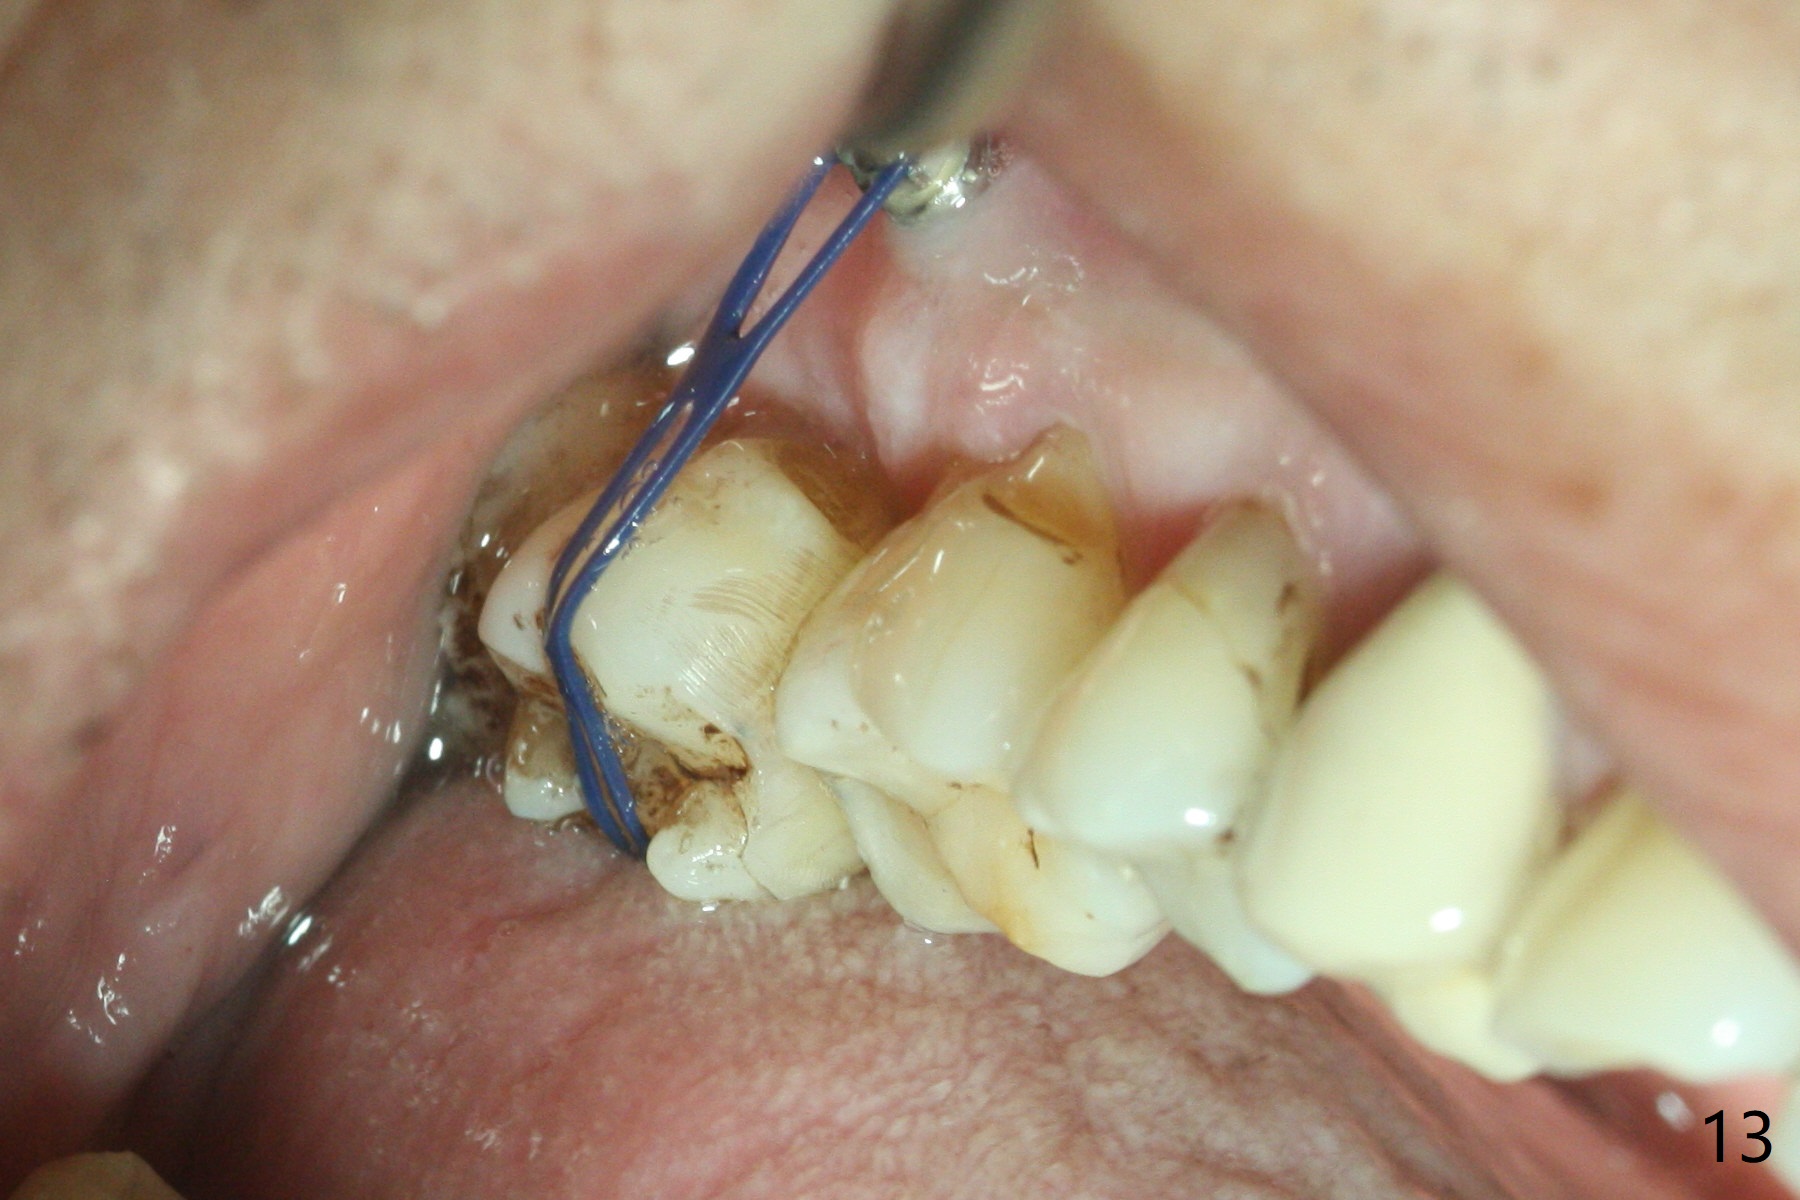

The buccal implant becomes loose in 2-3 months. When the wound heals (Fig.9 <), a 1.6x`10 mm implant is placed with the help of PAs for trajectory (Fig.10,11) and in the nonkeratinized gingiva (higher, the crestal bone may have been traumatized by previous implant placement, Fig.12). Two months later, the tooth #2 is partially intruded (Fig.13). A provisional (Fig.14 P) is fabricated in the osteointegrated implant at #31 with supraocclusion so that the remaining dentition has no occlusal contact (*). The periodontally compromised tooth #2 becomes in buccoversion in 2 months. The provisional is removed, while a lingual button is placed in the buccal surface of the tooth #2 (Fig.15). With power chain attached to the lingual mini-implant, the tooth #2 is lingualized in 2 months. The provisional and the implants are reused for final intrusion (Fig.16). The treatment is nearly 11 months. The buccal implant, although placed in the movable mucosa, remains stable and healthy (Fig.17). The tooth #1, as a guiding plane (to prevent #2 from distalization during intrusion), is not extracted after intrusion is completed.